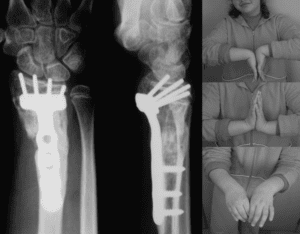

Common Conditions of the Hand